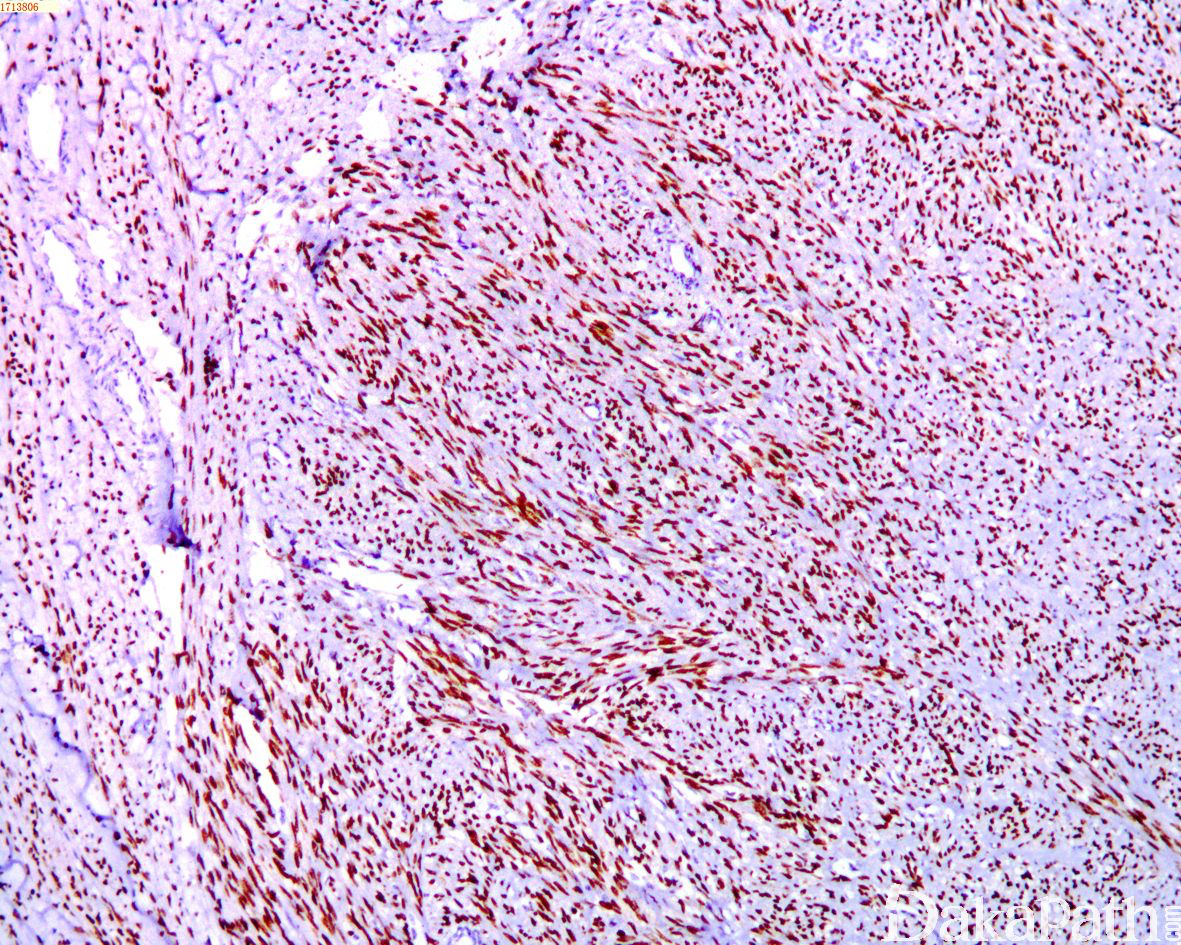

免疫组织化学染色:

Actin、Desmin、caldesmon 阳性,约 2/3 的肿瘤 ER、PR 以及 WT1 阳性,HMB45,Melan-A,CD34. S100. CK 阴性。